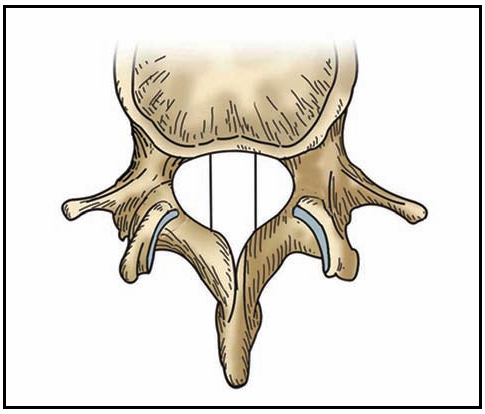

水平面:

以椎体后缘为界分1~4区,两侧椎弓根内界为1、2区,中1/3为1区(中央区);

左右1/3为左右侧 2 区(旁中央区);

椎弓根内外侧之间为 3 区(外侧区);

椎弓根外侧以外为4区(极外侧区)。

冠状面:

将骨性椎管矢状径分为四等份,从前至后一至四份分别命名为 a 域、b 域、c 域、d 域。